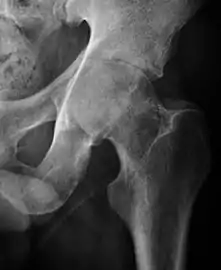

Projectional radiography ("X-ray") is currently useful not only in older people in whom osteoarthritis of the hip is suspected but also in younger people without osteoarthritis, who are being evaluated for femoroacetabular impingement (FAI) or hip dysplasia.[1]

Plain radiography allows us to categorize the hip as normal or dysplastic or with impingement signs (pincer, cam, or a combination of both). Besides these, pathologic processes like osteoarthritis, inflammatory diseases, infection, or tumors can also be identified (Figure 1).[1]

Figure 1.